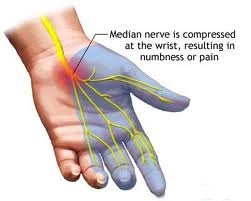

Radicular Pain: Ranges from a sharp pain shooting into the shoulder, elbow, wrist or hand to “pins and needles” tingling or simply in increased or decreased sensation in those areas.

Arm pain as mentioned above can come from various sources. However, it can also be indicative of something a more serious underlying cause as well such as originating from the spinal column in the Neck region. Herniated Disc